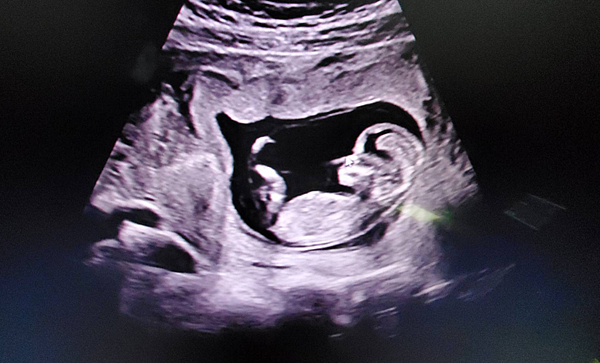

好在小北鼻在超音波照起來

基本上也是穩穩的按照週數在長大

不管回看幾次覺得小小的寶寶在肚子裡面動來動去真的是太可愛啦~